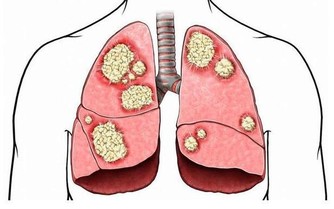

部分引起慢性便秘的病因危險性很大,如肛門損傷、腸梗阻、腸嵌塞或潰瘍、腸道惡性腫瘤等,此時最好及時到專科門診就診,以免延誤疾病診治。